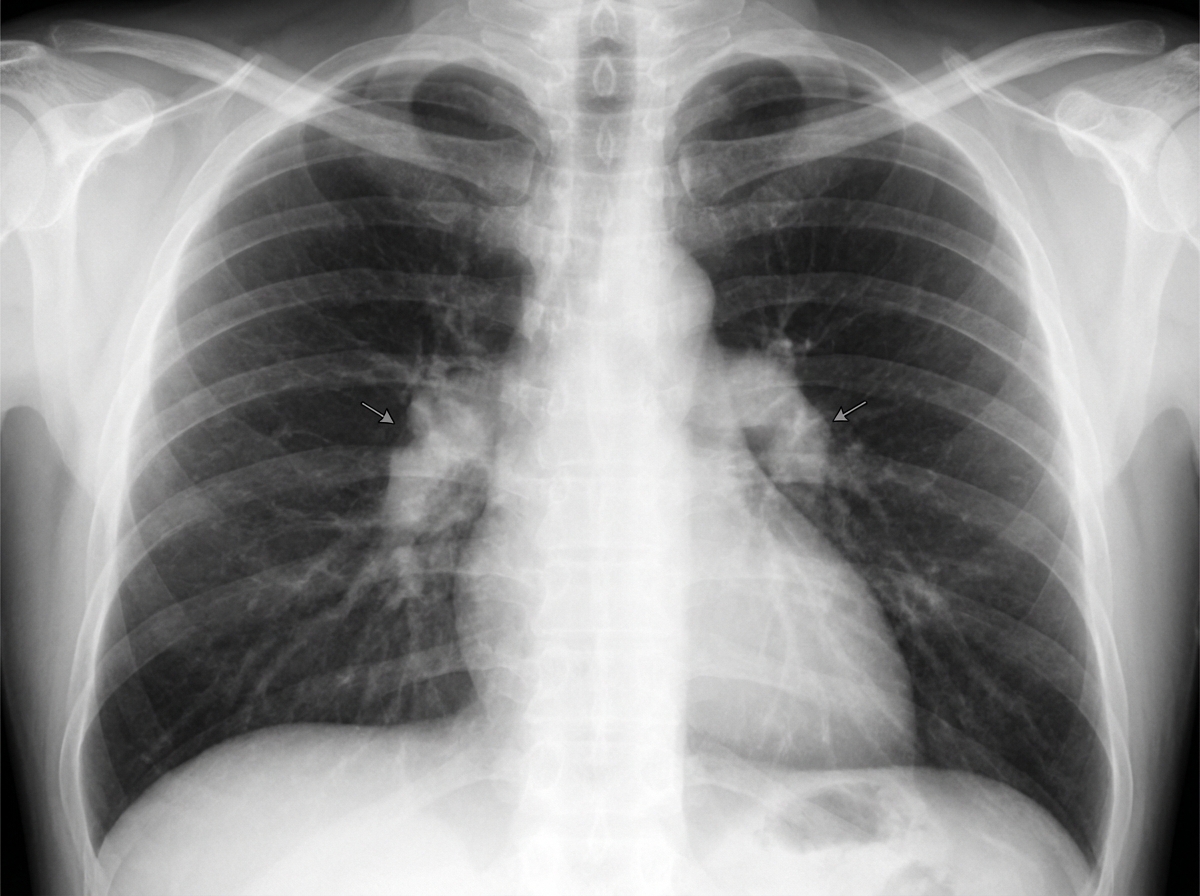

A 30-year-old African-American woman comes to the physician for a routine checkup. She feels well. She has a history of type 2 diabetes mellitus that is well-controlled with metformin. Her mother died of a progressive lung disease at the age of 50 years. The patient is sexually active with her husband, and they use condoms consistently. She has smoked one pack of cigarettes daily for the past 10 years. She drinks one to two glasses of wine per day. She does not use illicit drugs. Vital signs are within normal limits. Examination, including ophthalmologic evaluation, shows no abnormalities. Laboratory studies, including serum creatinine and calcium concentrations, are within normal limits. An ECG shows no abnormalities. A tuberculin skin test is negative. A chest x-ray is shown. Which of the following is the most appropriate next step in management?